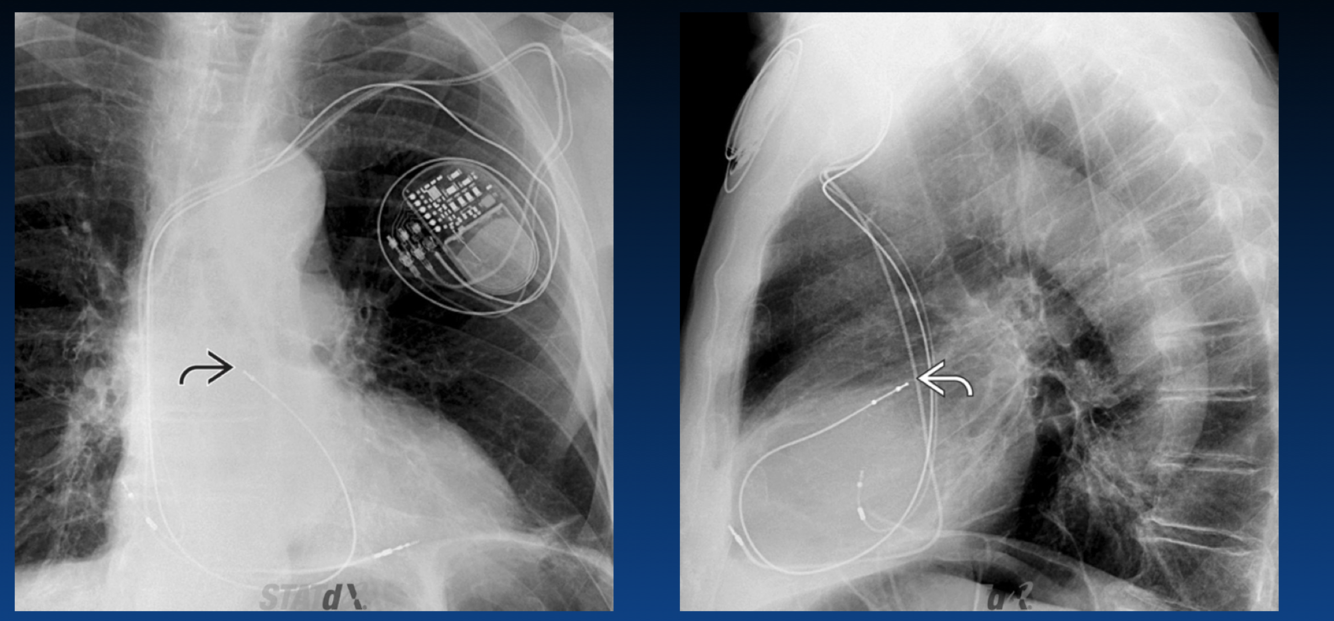

Name the Pacemaker/ICD Complication

Misplaced lead

What is Twiddler Syndrome?